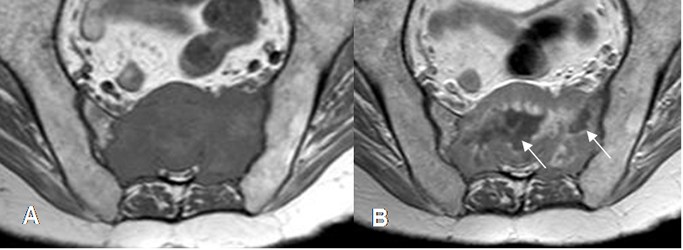

El PET es muy utilizado para el seguimiento post-quirúrgico, detectar recurrencia local o enfermedad metastásica. Es muy útil en casos donde el material metálico produce artefactos en la RM o TAC, que limitan la valoración. Igualmente se utiliza para evaluar la respuesta de quimioterapia adyuvante, en sarcomas. (2). (Fig 14).

Fig 14. Tomografía por emisión de positrones.

A: TAC axial y B: PET axial. Lesiones metastásicas en los alerones del sacro. (Flechas delgadas). Hay otras lesiones en ambos iliacos, no detectadas con el TAC, pero con aumento del metabolismo en el PET. (Flechas gruesas).